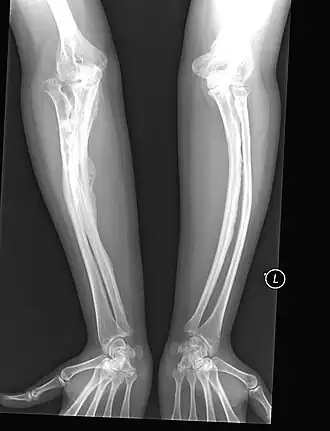

![]() несовершенный остеогенез V типа у взрослого | |